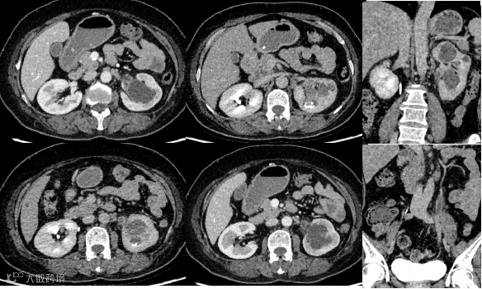

病例1

女,65岁

主诉:发现肉眼血尿20余天

现病史:患者20天前发现肉眼血尿,为全程血尿,同时伴有左侧腰痛不适,可放射至胸部,给予止痛药后可缓解。外院查腹部CT提示:左肾盂囊实性肿块。无寒战发热,无头晕头痛,无腹痛腹泻,无排尿困难,无咳嗽、咳痰 影像号:

2025-02-01 泌尿系CTU成像 影像号:3355669

2025-02-05 中腹部MR平扫 影像号:3357390

影像学表现